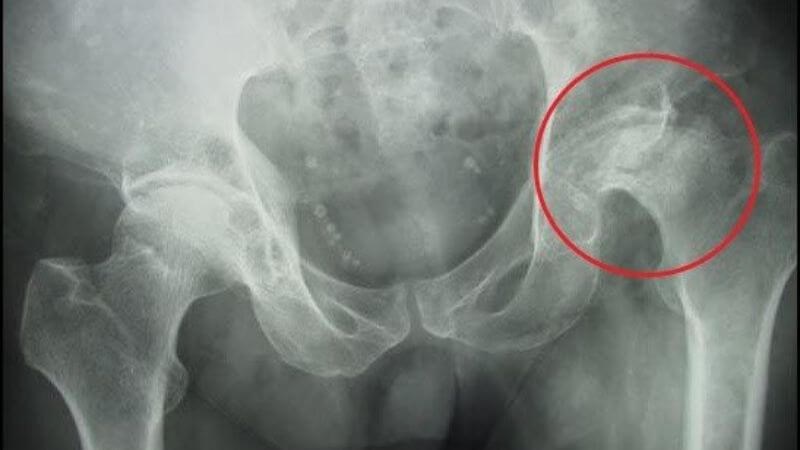

- Gãy cổ xương đùi: là gãy phần tiếp xúc giữa xương đùi và xương chậu.

Ngoài ra, người lớn tuổi có thể bị gãy xương này do loãng xương làm suy yếu các cấu trúc của xương trong đó có xương đùi. Một trong những tình trạng hay gặp của người lớn tuổi là gãy cổ xương đùi.[3]

Để đánh giá rõ vị trí cũng như loại chấn thương, bác sĩ sẽ chỉ định chụp X-quang hoặc chụp cắt lớp vi tính để đánh giá tình trạng gãy xương đùi. Một số loại gãy xương đùi bao gồm:

Chụp X-quang giúp chẩn đoán gãy xương đùi